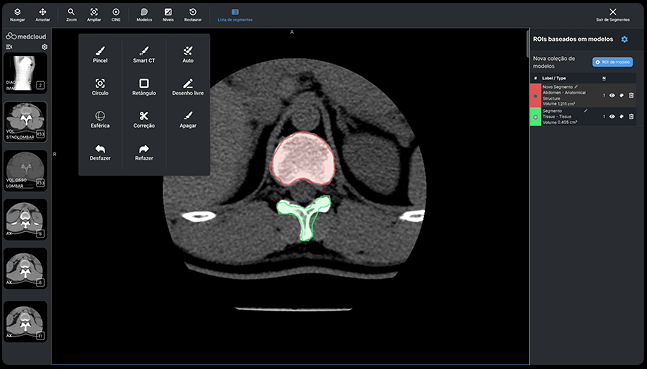

Herramientas con baja curva de aprendizaje. Su equipo se entrenó eficientemente en poco tiempo.

Con sólo unos clics y desde cualquier lugar. Trabajo de calidad y seguro en cualquier navegador de Internet.

Calidad diagnóstica en cualquier lugar, en cualquier momento y en el menor tiempo posible.

Calidad diagnóstica en cualquier lugar, en cualquier momento y en el menor tiempo posible.